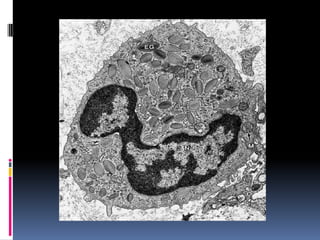

A - ERYTHROCYTES B- NEUTROPHIL C - EOSINOPHIL D - LYMPHOCYTE